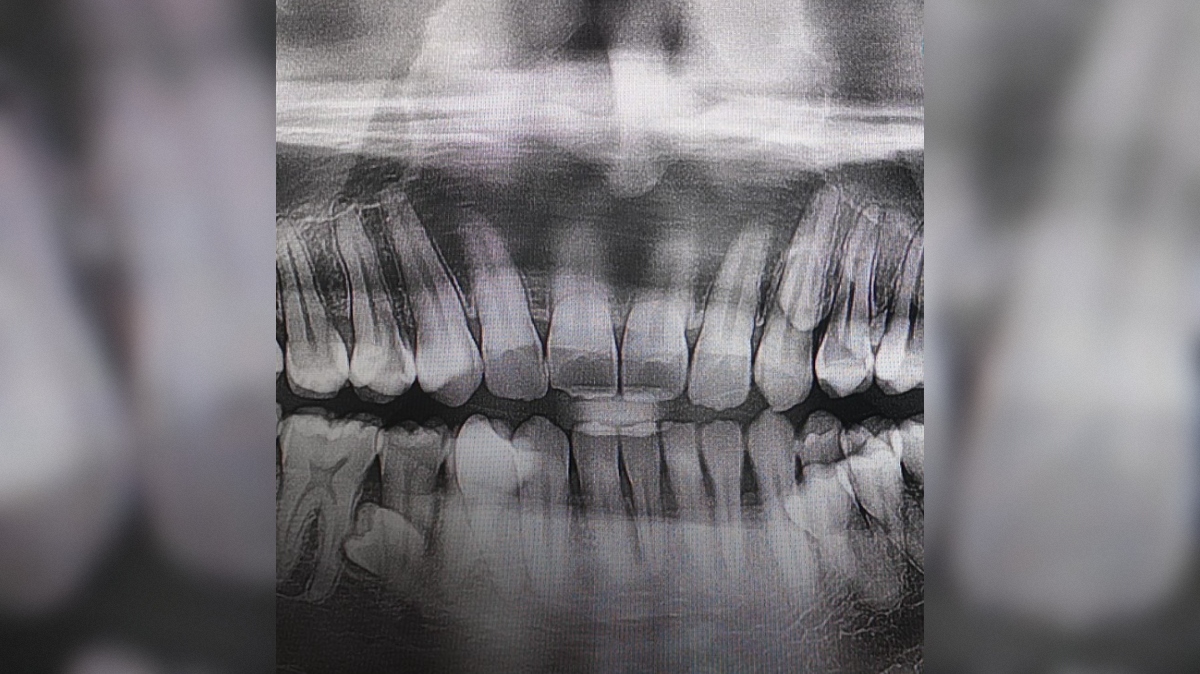

33-letni Prathab Muniandy ima kar 42 zob, medtem ko jih ima večina odraslih ljudi 32. Njegovo stanje se imenuje hiperdontija – redka anomalija, pri kateri se razvijejo dodatni zobje.

"Zobna rentgenska slika je pokazala, da so še štirje zobje, ki še niso izrasli. V začetku leta 2023 sem ugotovil, da imam skupno 42 zob."

Ob koncu leta 2023 se je odločil, da svojo posebnost prijavi za uradno priznanje. Prijavi je priložil zobozdravstveno dokumentacijo in rentgenske slike, ki so potrdile njegovo stanje. Ko je bil njegov dosežek priznan, je to opisal kot izjemno ponosen in nepozaben trenutek zase in za svojo družino.